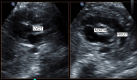

Diagnostic ultrasound (DUS) is, arguably, the most common technique used in obstetrical practice. From A mode, first described by Ian Donald for gynecology in the late 1950s, to B mode in the 1970s, real-time and gray-scale in the early 1980s, Doppler a little later, sophisticated color Doppler in the 1990s and three dimensional/four-dimensional ultrasound in the 2000s, DUS has not ceased to be closely associated with the practice of obstetrics. The latest innovation is the use of artificial intelligence which will, undoubtedly, take an increasing role in all aspects of our lives, including medicine and, specifically, obstetric ultrasound. In addition, in the future, new visualization methods may be developed, training methods expanded, and workflow and ergonomics improved.